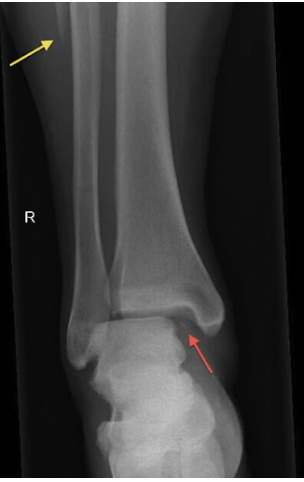

Maisonneuve Fractures

A Maisonneuve fracture represents a complex ankle injury involving syndesmotic and deltoid ligament disruption with an associated proximal fibular fracture, typically caused by an external rotation mechanism. Patients may have ankle pain, medial tenderness, proximal fibular pain, and difficulty weightbearing. Diagnosis requires careful evaluation with ankle radiographs for medial clear space widening and tibia/fibula imaging to assess the proximal fibula. These injuries are frequently misdiagnosed as isolated ankle sprains, leading to chronic instability and post‑traumatic ankle arthritis if untreated.